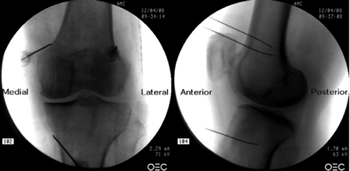

Fluoroscopy-guided genicular nerve radiofrequency

To perform a fluoroscopic-guided TRFGN, we need an anteroposterior (AP) and lateral view of the knee (Figure 2). First we place the patient in supine position with a pillow under the popliteal fossa (to make the patient more comfortable) (16). After performing asepsis and antisepsis of the knee, we proceed to locate the GN (Table II). SLGN is advancing the TFR needle toward the confluence of the lateral femoral diaphysis with the lateral femoral condyle in an AP view and at a mid-point of the femur in a lateral view. The SMGN is located by advancing the needle toward the confluence of the medial femoral diaphysis with the medial femoral condyle in an AP view and at a mid-point of the femur in a lateral view. Finally, the IMGN is located by advancing the needle toward the confluence of the medial tibial diaphysis with the tibial epicondyle in an AP view and at a midpoint of the tibia in a lateral view (16,17).

Fig. 2. Anteroposterior (AP) and lateral projection where therapeutic targets are observed using fluoroscopy. Image taken from Choi et al. (9). Reproduced with the permission of Jin Woo Shin.

Table II. Location of genicular nerves guided by fluoroscopy

Good AP and lateral view is very important. In AP projection, the tibiofemoral joint should have a similar width on both sides of the knee with the interspace open (9). In lateral projection, there must be a correct overlap of both femoral condyles to perform a satisfactory blockage of the SMGN and SLGN (18).

Most authors take the references described above to locate these nerves by fluoroscopy, except Fonkoué et al. (18), who find that the therapeutic targets of SMGN and SLGN (in a lateral view) are at the junction of the upper edge of their respective femoral condyles with the posterior cortex of the femur diaphysis, and not in half the thickness of the femur, as described classically (9,10,13).

Because the success of the TRF of the genicular nerves depends on the correct location of the RF needle tip (as close as possible to the nerve), Know et al. (17) demonstrated with magnetic resonance imaging that the points used classically in fluoroscopy for ablation of the three genicular nerves (SMGN, SLGN and IMGN) are correct. They observed that GN passes through the intersection formed by the diaphyseal and metaphysis line of the distal femur or proximal tibia (SLGN 92 %, SMGN 88 % and IMGN 100 %).